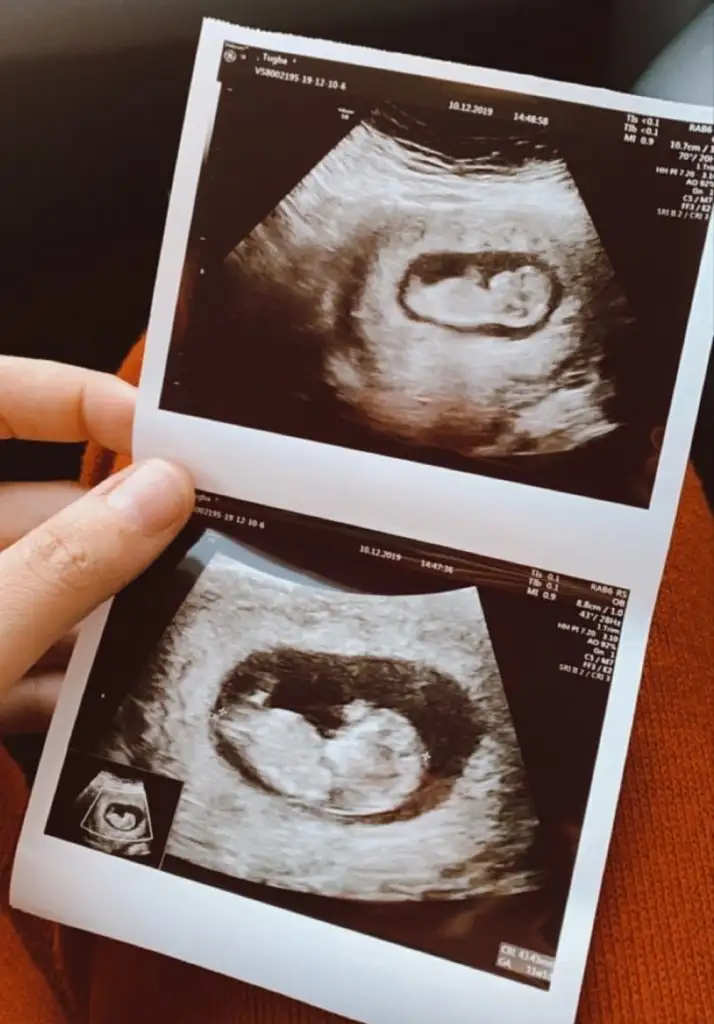

Kız gibi kafa şekli ama tutmaya bilirHaftaya tekrar gidicem onda 12 haftalik olcak , keske net olsaydi ya cok merak ediyom hele bidaha bakin![]()

10+2 hafta nub iki tarafa benzer 11+ yada 12+ olmalı usg ama şimdilik erkek gibi gibi ekliyorumIkra meyra cnım bu arkadaşın 10+2 sence Belli mi kız gibi geldi bana ☺

Kaç haftalık sanki kız gibi ama 11+ yada 12+ olmalı usg buyuk görünüyor gibi 13+ sonrası organ tamamlanmış oluyorMerhabalar bu bebise de bakar misiiz kiz mi erkek mi

Hadi ya bu da mı erkek acaba bi erkek oğlu daha var da açıklanınca haber verirm artık teşekkürler canım10+2 hafta nub iki tarafa benzer 11+ yada 12+ olmalı usg ama şimdilik erkek gibi gibi ekliyorum![]()

Şimdilik erkek gibi 11 yada 12 hafta usg paylaşın daha net olur nubuHadi ya bu da mı erkek acaba bi erkek oğlu daha var da açıklanınca haber verirm artık teşekkürler canım ☺